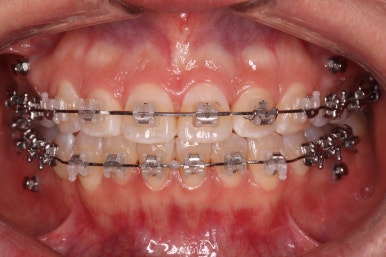

윗니는 발치를 했고, 잇몸뼈에 미니스크류를 식립하여 앞니를 뒤로 당겨넣고 있습니다.

아랫니는 아직 덜 가지런해졌네요.

이 뽑은 자리가 점점 줄어드는 것이 보입니다.

아랫니도 많이 가지런해졌네요.

이 뽑은 자리가 반 이상 줄어든 것 같네요. 아랫니는 마무리를 해도 될 정도로 많이 좋아졌습니다.

이 쯤되면 중간평가를 하게 됩니다.

입 모양을 보고 얼마나 더 넣을지, 앞으로는 어떤 방향으로 치료하게 될 지 다시 한 번 점검하는 것이지요.

처음 보다는 입이 많이 들어갔습니다.

다만 아직 턱끝에 힘이 들어가는 것을 봐서 입을 더 넣어야 될 필요가 있어 보입니다.